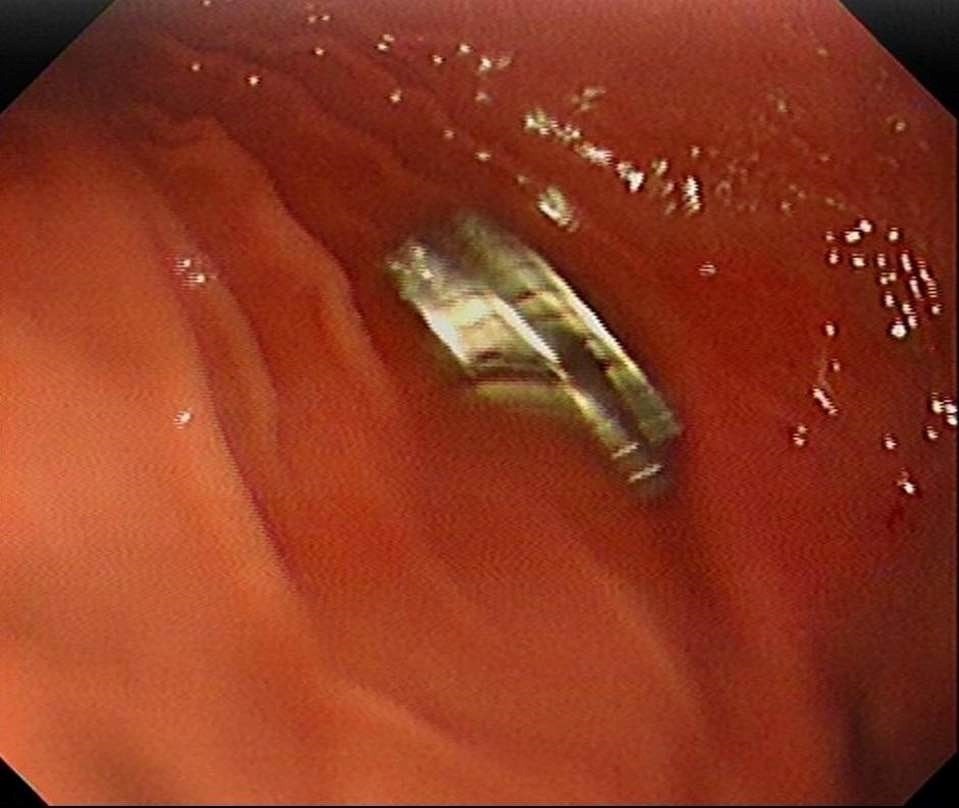

Fırat Üniversitesi Çocuk Gastroenteroloji Hepatoloji ve Beslenme Bilim Dalı Başkanı Prof. Dr. Yaşar Doğan, çocuk hastanın yemek borusuna yapışmış 19 mıknatısı endoskopik yöntemle çıkardı.

Mıknatıslar uzun süre yemek borusunda takılı kaldığı için yemek borusu ve mide girişinde zedelenmeler olurken, çocuğun sağlık durumunun iyi olduğu ve taburcu edildiği öğrenildi.